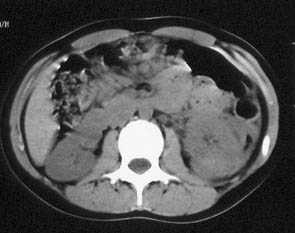

肾挫裂伤03

女性,16岁,3小时前骑自行不慎跌落小溪,左侧躯体着地,背痛,无呕。体检:胸左侧季肋部皮肤擦伤,腹稍胀,左上腹轻压痛。

ct平扫:左肾稍肿大,肾实质密度稍欠均匀,肾包膜下见略高密度影,ct值55hu,右肾未见异常。

ct诊断:左肾挫裂伤,并肾包膜下积血。